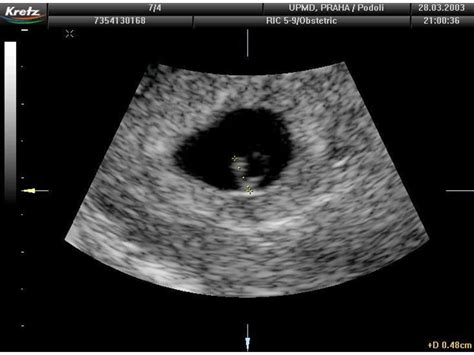

Prvotrimestrální screening je ultrazvukové vyšetření plodu prováděné v prvním trimestru těhotenství. Jeho hlavním cílem je odhalit případná chromozomální onemocnění plodu, jako je například Downův syndrom, Edwardův syndrom nebo Patauův syndrom. Kromě toho může screening poskytnout informace o celkovém vývoji plodu a jeho anatomii.

- Ultrazvukové vyšetření: Provádí se mezi 11. a 14. týdnem těhotenství. Lékař zhodnotí několik parametrů plodu, včetně jeho velikosti, srdeční akce, přítomnosti nosní kosti a tloušťky nuchální kůže (tzv. nuchální translucence).

Na základě výsledků krevních testů a ultrazvukového vyšetření je vypočítáno riziko přítomnosti chromozomálních vad u plodu. Je důležité si uvědomit, že screening není diagnostické vyšetření, ale pouze odhaduje riziko. V případě vyššího rizika může lékař doporučit další, invazivnější vyšetření, jako je odběr plodové vody (amniocentéza) nebo odběr choriových klků (CVS).